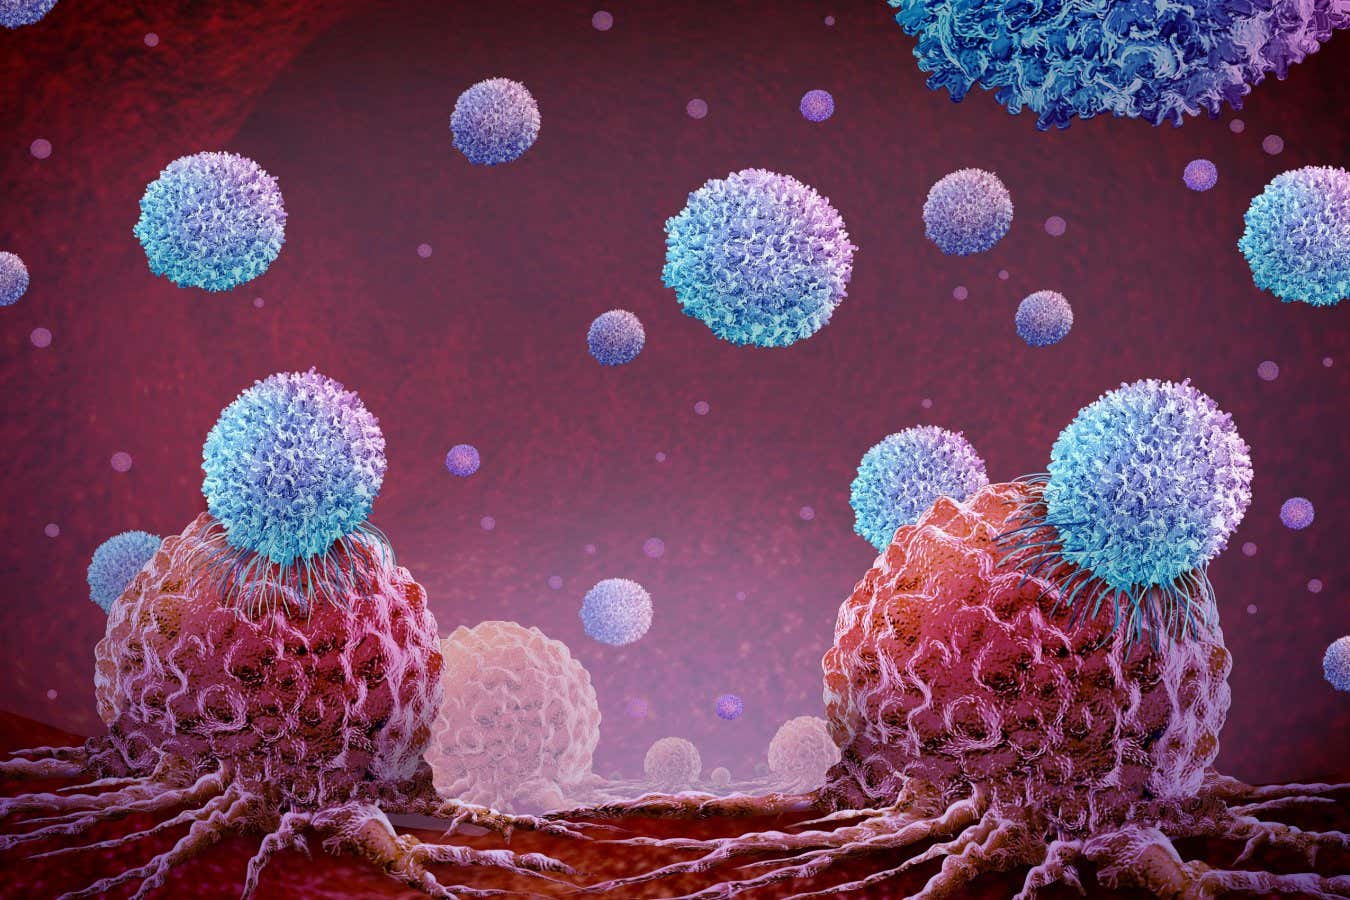

CAR T-cells are T-cells – immune cells that usually kill infected or cancerous cells – that are taken from the person undergoing treatment. In the lab, they are genetically engineered to make them attack a specific target and then infused back into that person.

To treat the woman, Müller’s team made CAR T-cells that target the immune cells that produce antibodies. When the modified cells were infused into her, they killed off her antibody-producing cells.

The CAR-T approach has shown promise for a wide range of autoimmune conditions, including lupus, multiple sclerosis, colitis and severe asthma. When CAR T-cells are used to treat cancers they often trigger serious side effects, but this is not being seen with autoimmune conditions. These side effects might be a result of killing huge numbers of cancerous cells, says Müller. With autoimmune conditions, far fewer cells need to be killed.

So far, most people treated for autoimmune conditions via CAR T-cell therapy have remained disease-free, Benjamin says, but there have some cases where the self-targeting cells have reappeared and another CAR-T treatment was required.